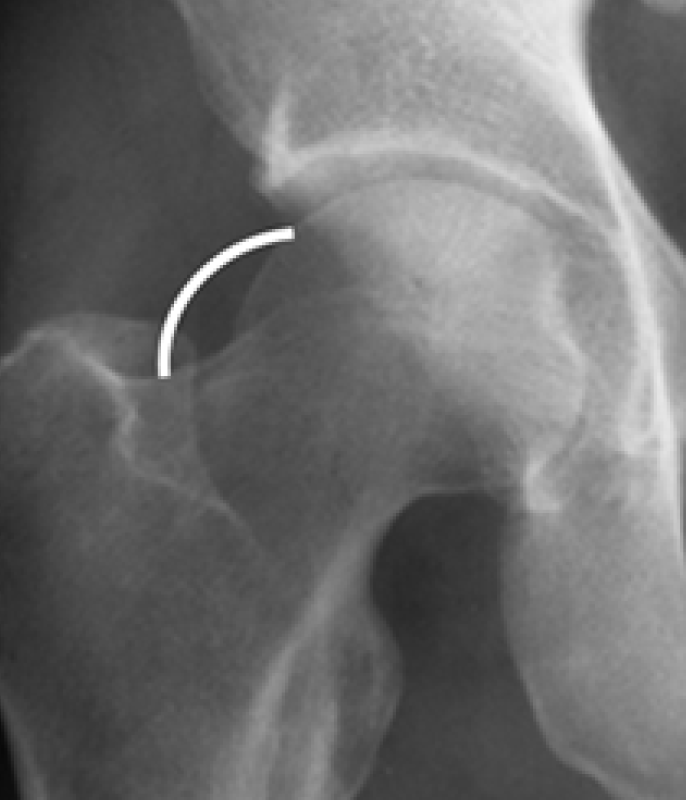

Pinzamiento tipo CAM